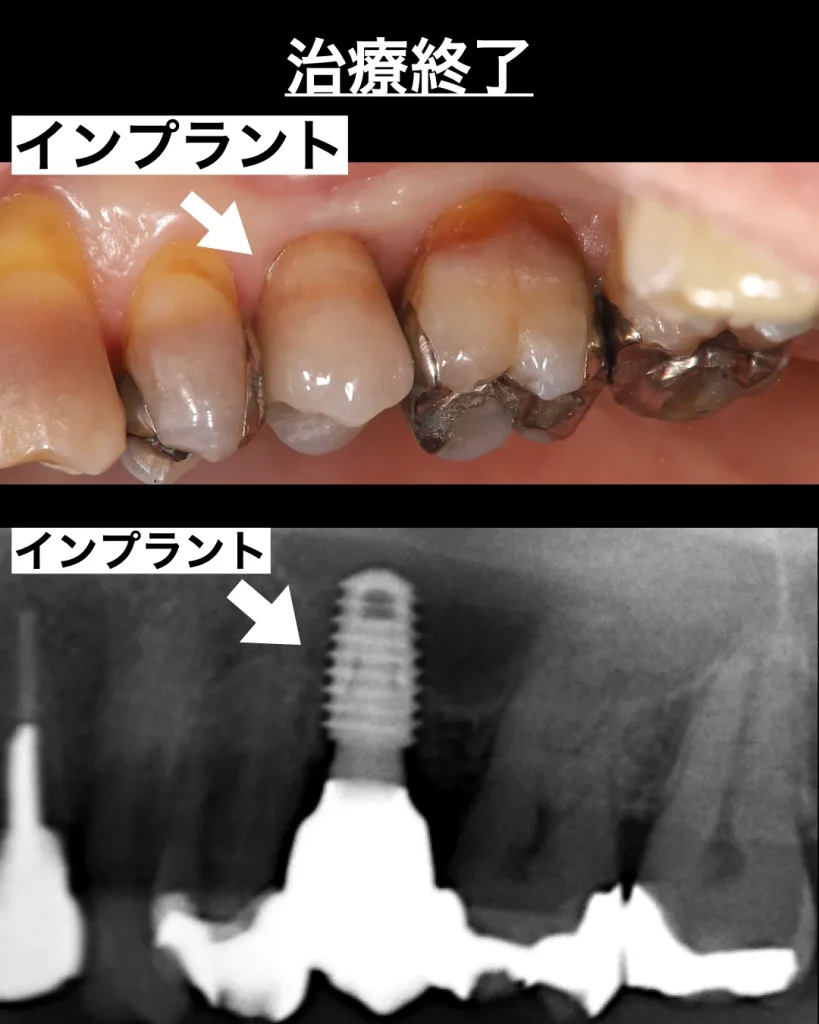

最終的な被せ物を装着

被せ物の型取りはすべて口腔内スキャナーで行います。以前は粘土状の印象材を使用していましたが、今はその必要がなくなりました。当院がお願いしている技工士は日本でもトップレベルの技工士なので、色も形態も美しくマッチングされた状態で作製していただけます。

特に今回の患者様の歯はテトラサイクリン歯といって、歯の発育過程においてある種の薬の服用により、グラデーションのきつい色に変色してしまっています。患者様のご要望から周りの歯の色に合わせてほしいとのことでしたので、技工士に正確な色の写真を送り作製していただきました。色も1回で合い、周りの歯とまったくわからないほど自然に仕上がり、さらによく噛めるので患者様は大喜びでした。治療期間は3ヶ月ほど、手術は1回で問題なくインプラント治療は終了しました。